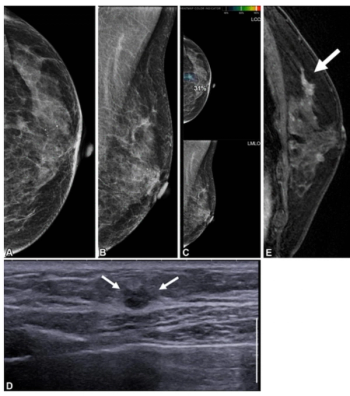

For DBT breast cancer screening, 47 percent of radiologist-only flagged false positives involved mass presentations whereas 40 percent of AI-only flagged false positive cases involved benign calcifications, according to research presented at the recent American Roentgen Ray Society (ARRS) conference.